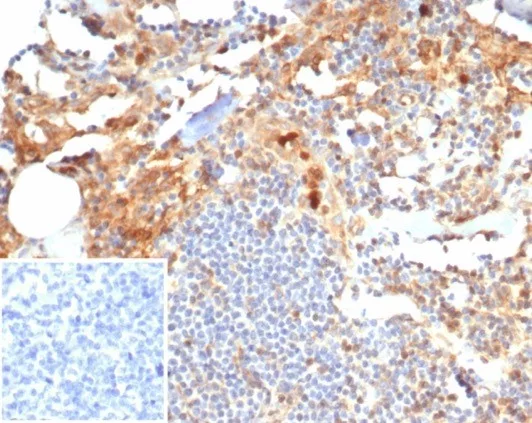

Immunohistochemistry (IHC)

1-2ug/ml

30 min at RT. Staining of formalin-fixed tissues requires heating tissue sections in 10mM Tris with 1mM EDTA, pH 9.0, for 45 min at 95°C followed by cooling at RT for 20 minutes

Positive Control

Human pancreatic adenocarcinoma|placenta or spleen tissue.